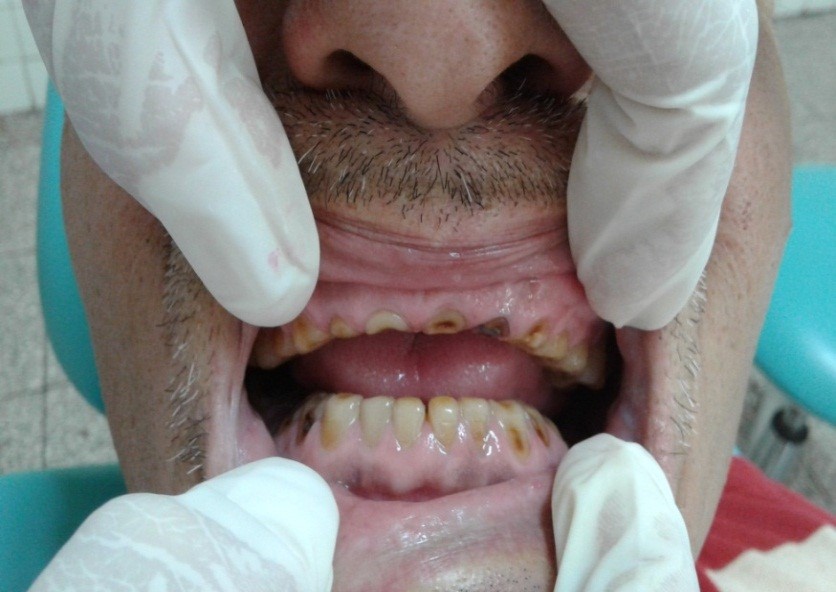

Volver a los detalles del artículo Sobredentadura parcial en adulto mayor con bruxismo